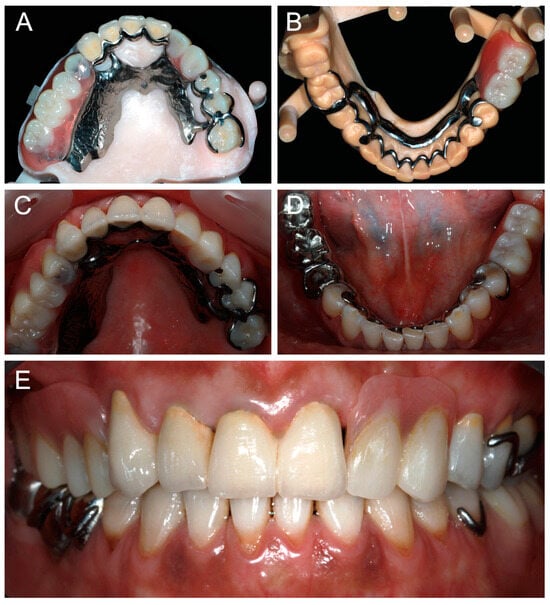

FDPs and RPDs were tried-in intraorally. Stability, retention, esthetic, phonetics, and occlusion were evaluated. Minor adjustments were made where needed. FDPs were definitively cemented and the RPDs were inserted (Figure 7). Occlusion was again verified. Maintenance instructions and oral hygiene methods were provided to the patient.

Figure 7. Occlusal views of maxillary and mandibular definitive prostheses: (A,B) on the printed casts; (C,D) in clinical situation; and (E) frontal view of prostheses in clinical situation.